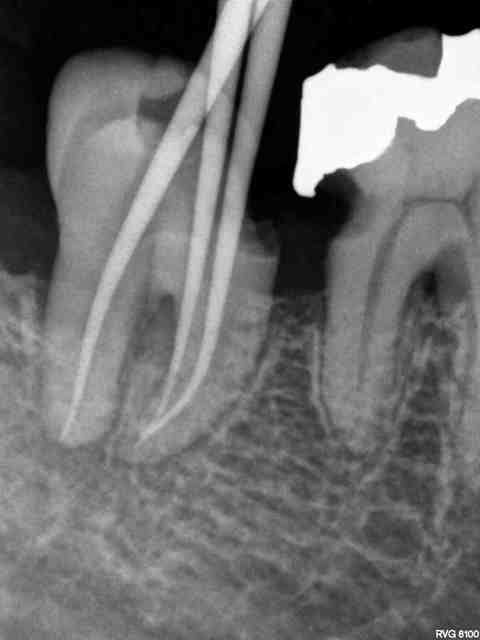

Risque de complication augmenté chez les patients fumeurs stressés mauvaise hygiène. Admirez la disparition du septum de ce patient fumant 40 cig/j, hyperstressé et à l'hygiène dégueulasse...

Avant anesth mcaety - Eugenol

en même temps si tu reprends ta rétro initiale atteinte de furcation sur les deux molaires et je suis surpris de voir que personne ne t'ai encore dit que la digue aussi avait disparu à l'essayage des cones mais dans ce cas précis et vu le contexte tout ça ne va pas tenir longtemps pas de surprise...

Je crois que bagherra émet l'hypothèse que la lésion osseuse interdentaire, apparue entre les deux séances, soit due à une intraligamentaire. (bagherra?)

Effectivement, il n'y a que 1 mois entre les deux radios. La 46 est pour l'instant bien vivante. Il y a eu une gingivite nécrotique après dans les jours qui ont suivi l'anesthésie intraligamentaire.